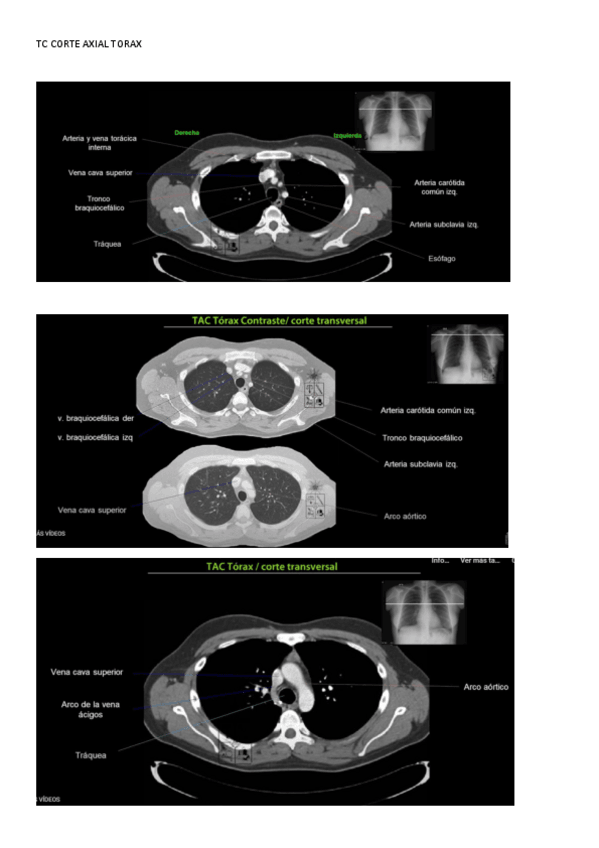

Imagen para el Diagnóstico y Medicina Nuclear

Anatomía por la Imagen